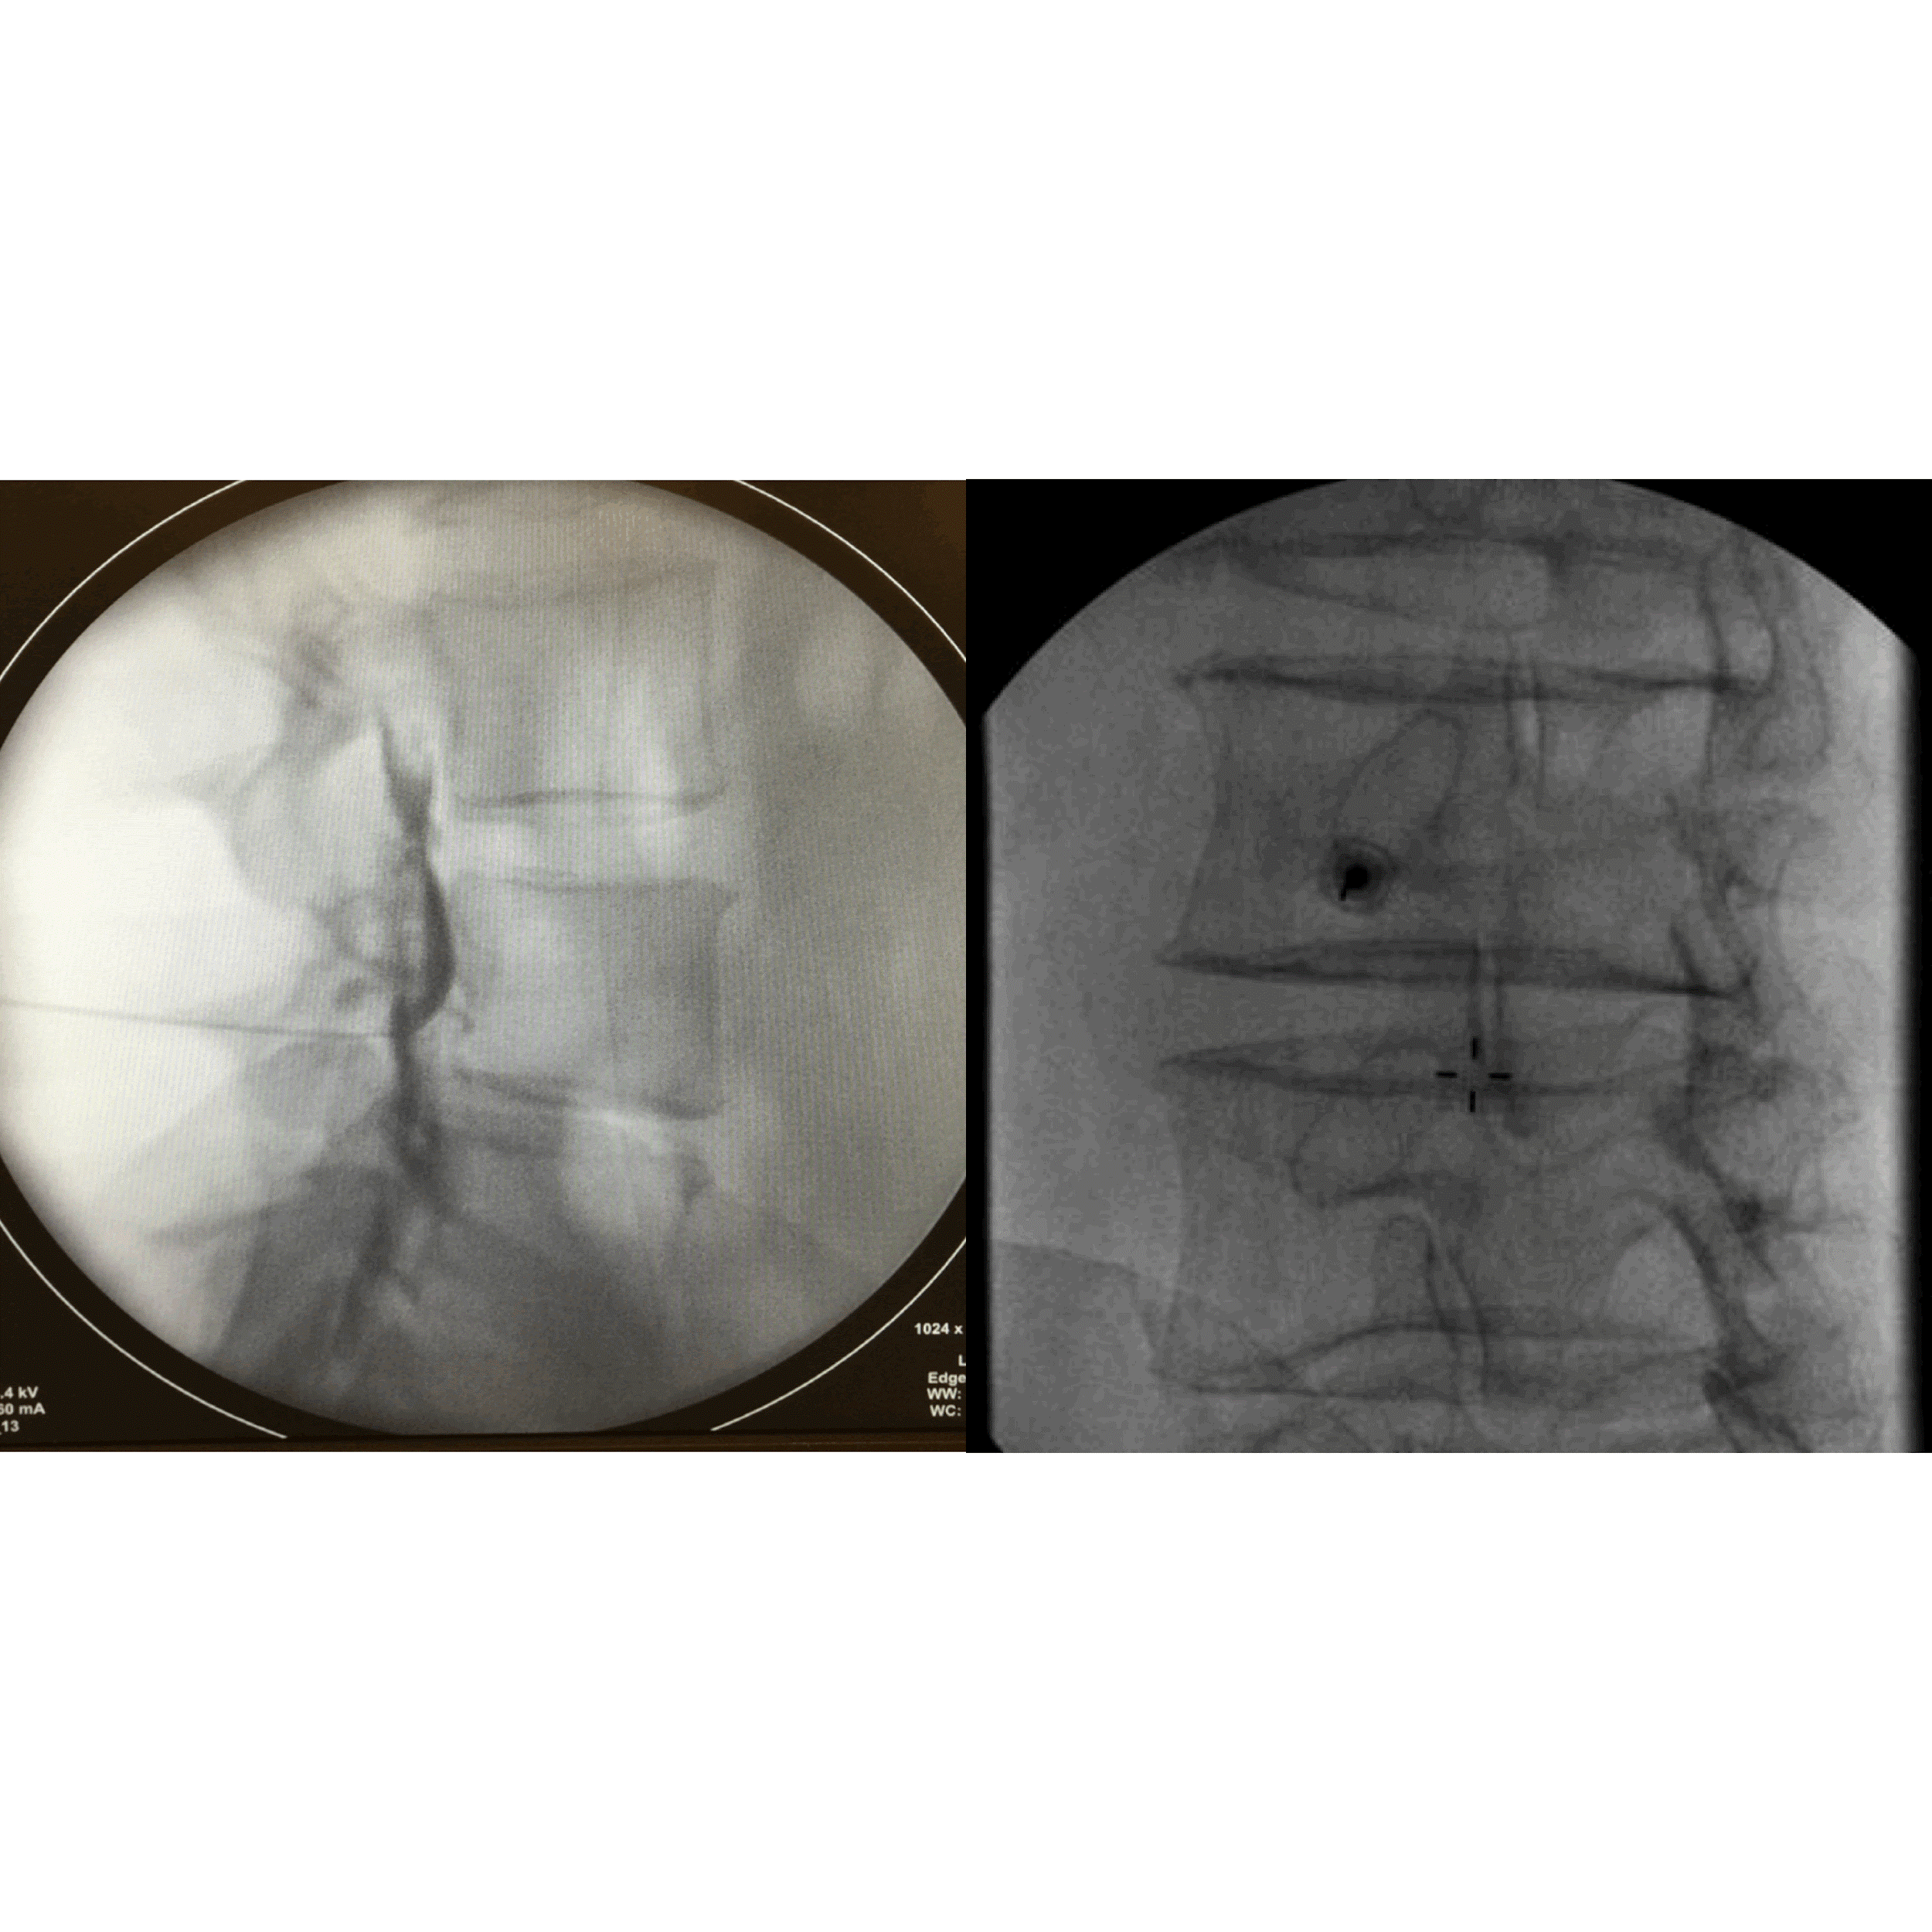

Transforaminal epidural injection

For the transforaminal route, patients were positioned prone on a radiolucent table, and the area was cleaned with povidone-iodine and alcohol, followed by sterile draping. The affected nerve root level was identified using fluoroscopy. Under oblique fluoroscopic guidance, the needle insertion site was marked at the eye of the “Scotty dog,” corresponding to the target neural foramen. After administering 1 mL of 2% lignocaine for local anesthesia, a 22G spinal needle was inserted at a 30–45° angle toward the foramen. The needle was advanced under continuous fluoroscopic guidance, with adjustments made using both oblique and lateral views. Once the needle tip reached the posterior aspect of the foramen, a test injection of 0.5–1 mL of contrast dye was administered to confirm proper epidural spread and avoid intravascular placement. The therapeutic injection consisted of 1 mL of 2% xylocaine and 1 mL (40 mg) of methylprednisolone acetate (Fig. 2).